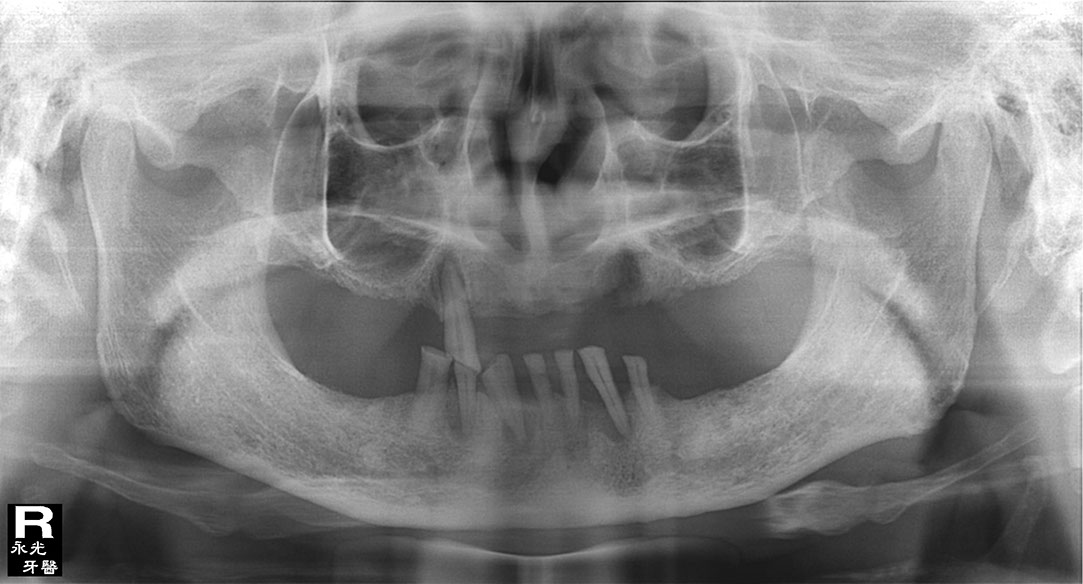

Implant 118a4.jpg

光牙醫